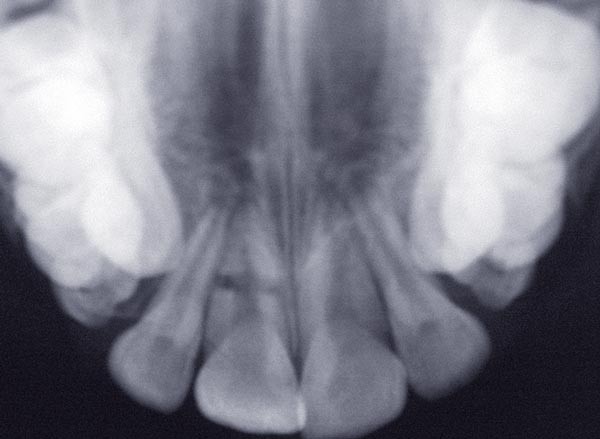

À l’examen clinique, le fragment coronaire peut être mobile, déplacé(fig. 1 et 2) et présenter une dyschromie transitoire de la couronne. Dès lors, un certain nombre de tests complémentaires s’impose.

La mobilité. Le degré de mobilité dépend de la situation du trait de fracture [4]. Plus la situation est coronaire, plus la mobilité est importante. Lorsque le trait de fracture est situé au tiers apical, la mobilité peut être physiologique et souvent, dans ce cas, la fracture radiculaire est mise en évidence lors de l’examen radiographique.